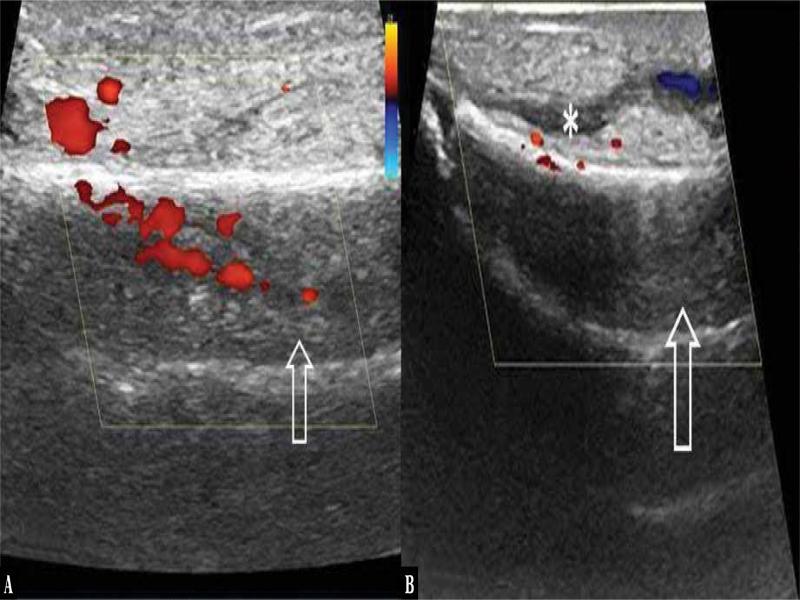

Fig. 3.

| Increased vascularity within or around the periosteum on colour Doppler | 4 | 80 |